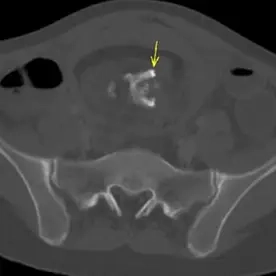

Die kontrastmittelverstärkte CT des Beckens zeigt eine 10 x 10 x 13cm große Raumforderung mit dicker Wand mit teils lipomatösen, teils nicht lipomatösem weichteiläquivalentem Inhalt, im Zentrum der Raumforderung besteht zudem eine Ossifikation (Pfeile), die den Aspekt einer Kieferanlage mit reifen Zähnen besitzt. Der CT-morphologische Verdacht eines reifen Teratoms. Bild einer Stieldrehung mit venöser Kongestion und Nekrose des betroffenen Adnexes.

CT-morphologischer Verdacht eines reifen Teratoms . Die klinische Symptomatik ist durch eine Stieldrehung mit venöser Kongestion und Nekrose des betroffenen Adnexes erklärbar.